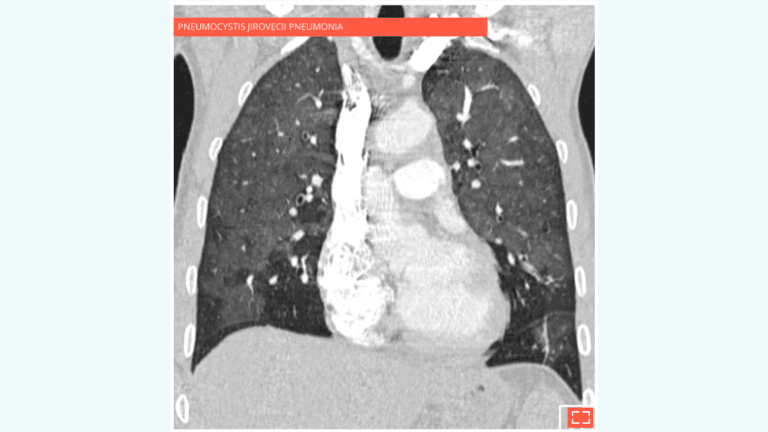

• Ground-glass opacity can be associated with various conditions:

• Pulmonary oedema

• Pulmonary infection: pneumocystis jirovecii pneumonia, cytomegalovirus (CMV), etc.